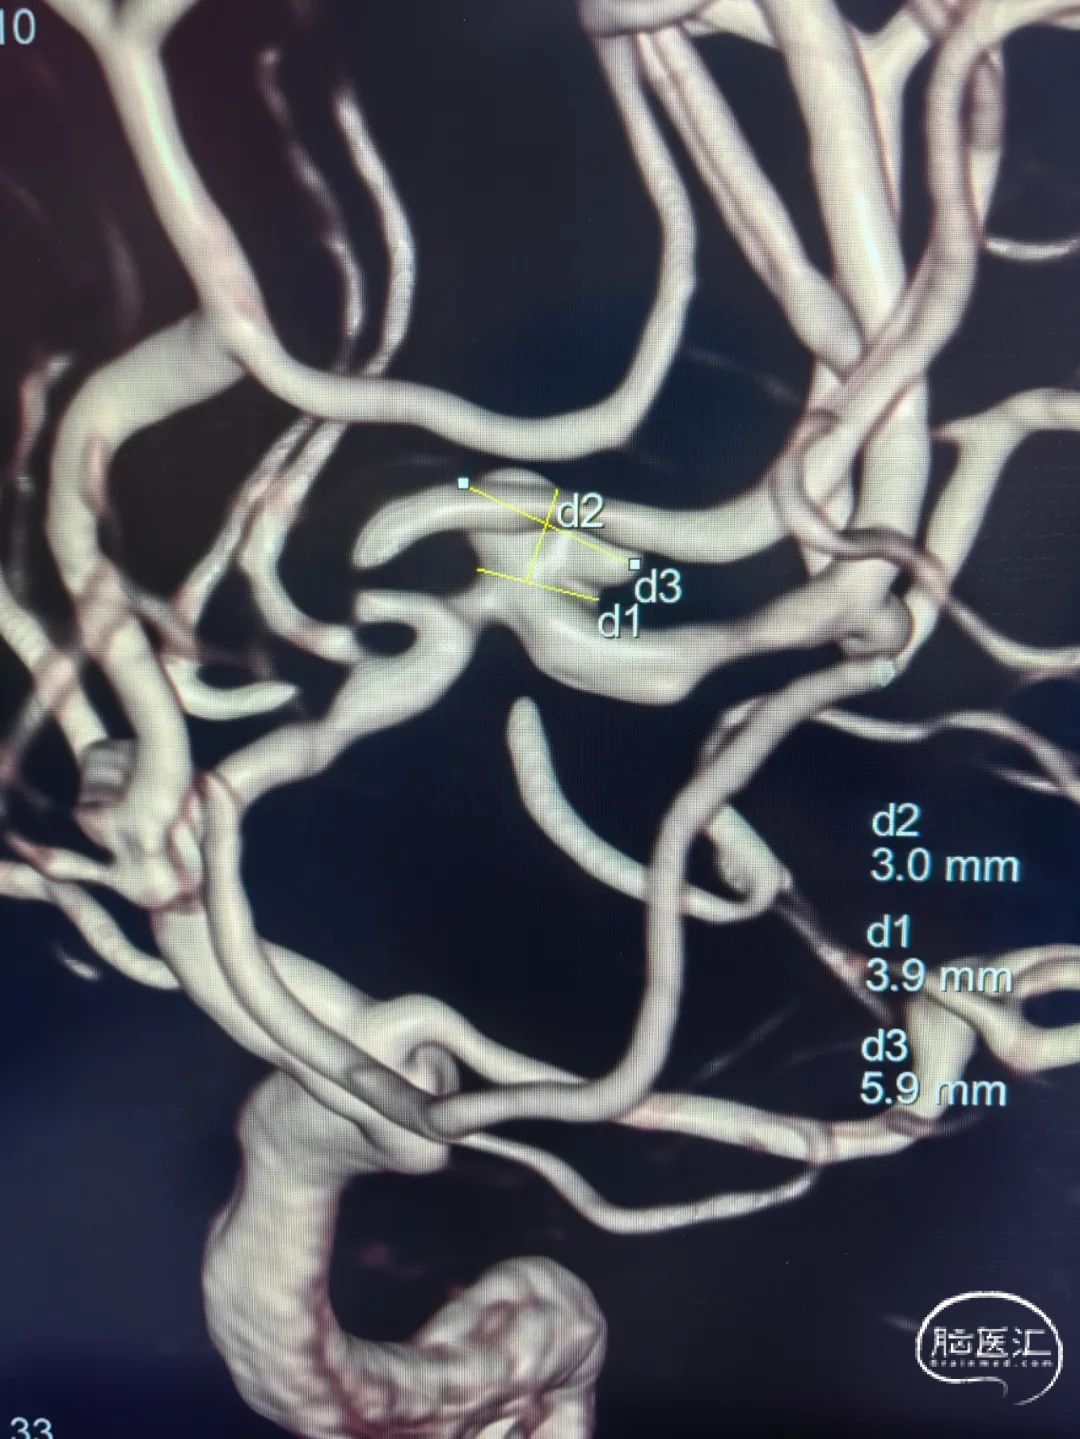

术前影像

左侧大脑中动脉M2段动脉瘤,前交通动脉瘤栓塞术后。

颅内动脉瘤的介入手术治疗越来越普及,对于颅内远端动脉瘤、载瘤动脉迂曲、行径血管迂曲的病人,中间导引导管的柔韧性、高到位性以及整体系统的支撑性成为动脉瘤栓塞成功的关键因素。本例手术为一例M2段动脉瘤,位置较远且入路行径动脉迂曲,Tethys®中间导引导管的通过性以及相对位置的支撑性保障了支架辅助弹簧圈顺利治疗该例病变。

动脉瘤位置特殊且形状不太规则,微导管往往不太稳定且对弹簧圈的栓塞能力具有较高的要求,本例手术同时使用了Jasper®弹簧圈,具有成篮稳定、柔软、顺应性高及解脱性好等特点,帮助致密栓塞。